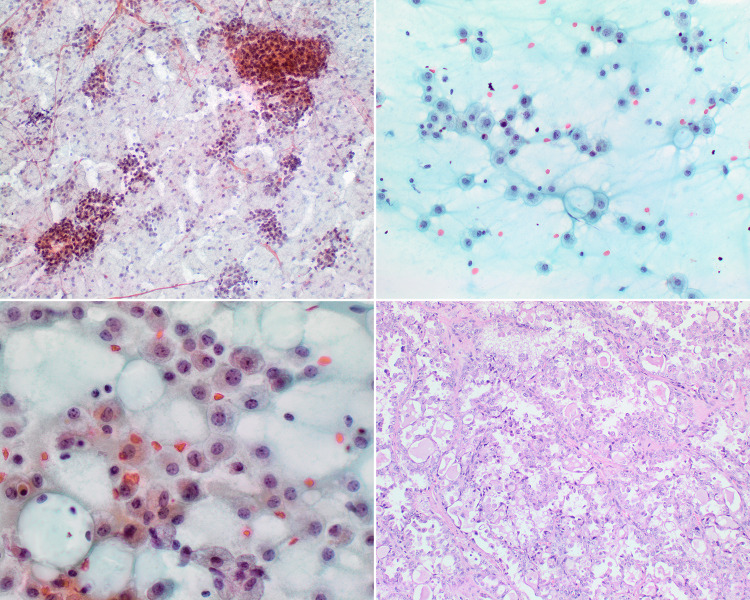

Fig. 14.

Secretory carcinoma. (Upper left) FNA showing cohesive epithelial clusters and dispersed cells associated with background proteinaceous cyst material (Papanicolaou stain, magnification × 10). (Upper right and lower left) Dyshesive histiocyte-like epithelial cells are shown with bland nuclear features and background mucin (Papanicolaou stain, magnification × 40). (Lower right) Tumor showing a papillary-microcystic growth pattern. Note the homogeneous colloid-like luminal secretion (H&E stain, magnification × 20)